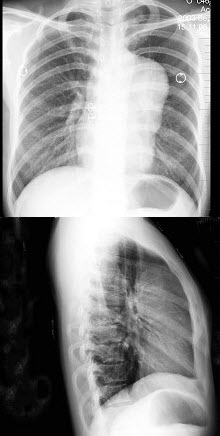

D.食管型颈椎病

E.以上都不是

161、单项选择题

男,38岁,感胸闷气逼2周余,近来加剧,不发热,X线检查如图,最可能的诊断是()

A.右侧肺不张

B.右侧胸膜肥厚

C.右侧大量胸腔积液

D.右侧中量胸腔积液

E.右侧气胸

186、单项选择题

女,32岁,感胸闷、胸痛,X线检查如图,最可能的诊断是()

A.畸胎瘤

B.胸腺瘤

C.淋巴瘤

D.胸骨后甲状腺肿

E.神经源性肿瘤